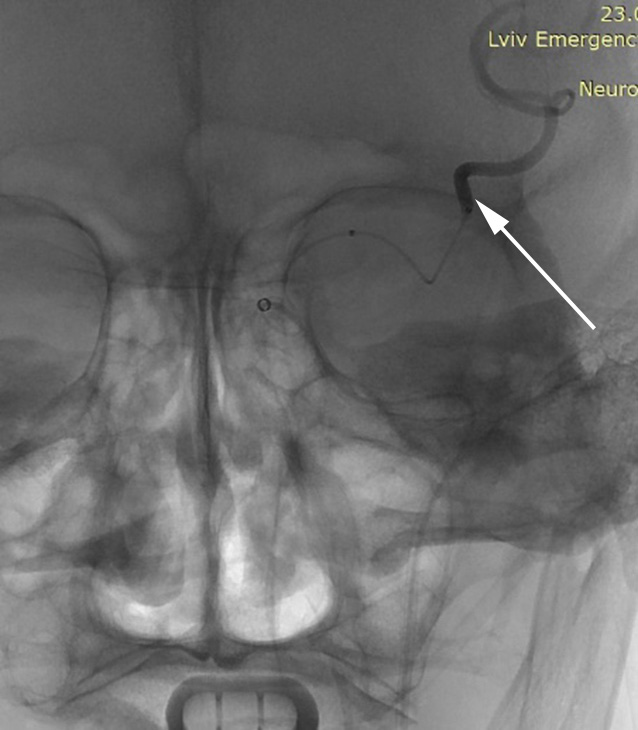

In all cases, direct intraoperative AP measurements were performed in the С1-segment of the internal carotid artery (ICA) proximal to the site of occlusion, both before and after thrombectomy (ICA-pre and ICA-post, respectively), and in the М1-segment of the MCA at the occlusion site prior to MT (MCA-pre) (Fig. 1).

A B C

Fig. 1. Catheter positioning during invasive AP measurement: A – in the internal carotid artery (ICA) before thrombectomy (via aspiration catheter); B – in the middle cerebral artery (MCA) distal to the thrombus (via microcatheter); C – in the ICA after thrombectomy. Arrows indicate the location of the distal catheter markers